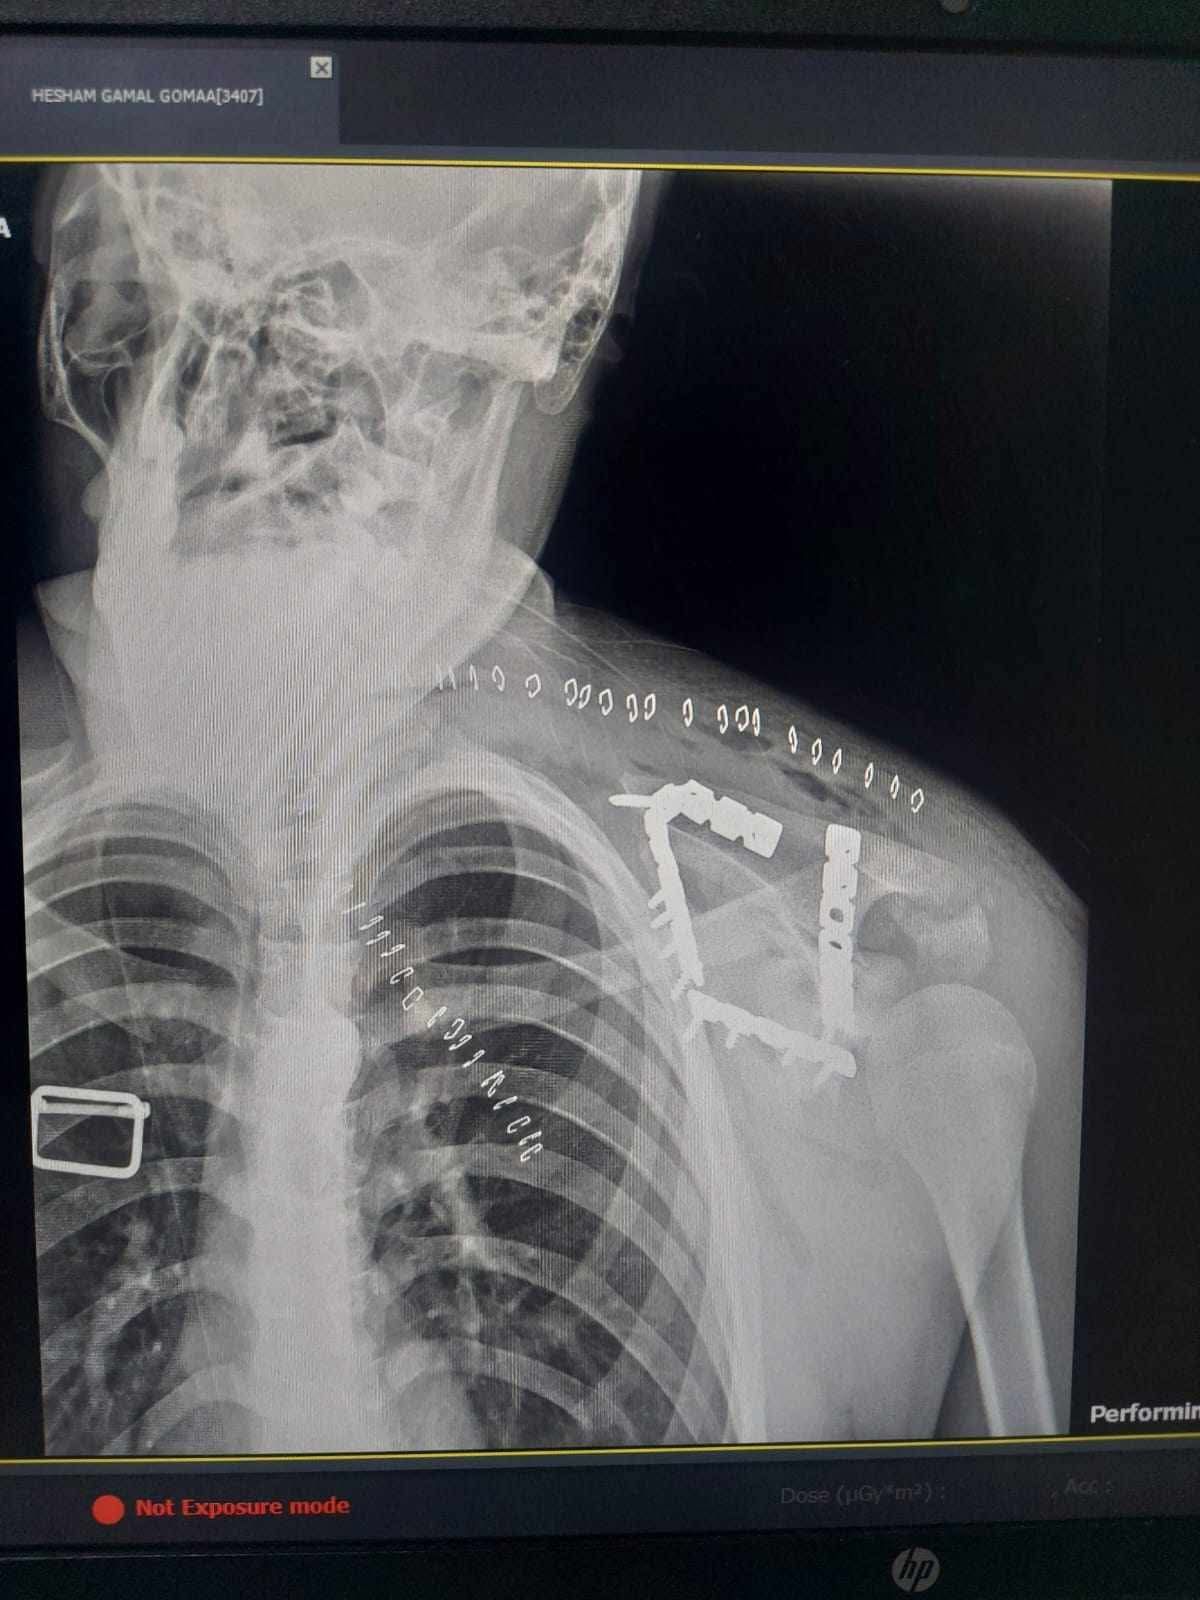

كان استقبل مستشفى التأمين الصحي بالفيوم شابًا يبلغ من العمر 17 عامًا، يعاني من كسر مفتت بعظمة لوح الكتف (Scapula)، وهي من الإصابات الدقيقة التي تتطلب مهارة عالية وتدخلًا جراحيًا متخصصًا.

خضع المريض لعملية جراحية معقدة استمرت نحو 4 ساعات تحت تأثير التخدير العام، تم خلالها رد وتثبيت الكسر بإستخدام الشرائح والمسامير.